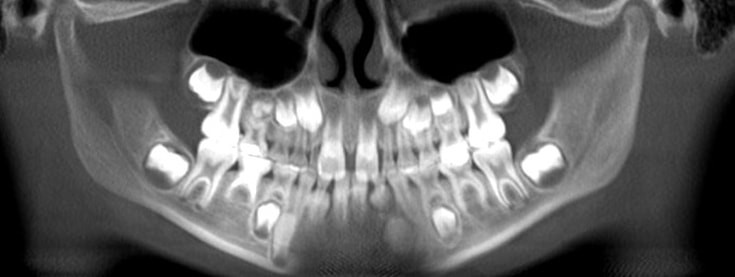

1. How old is the patient with the following X ray?